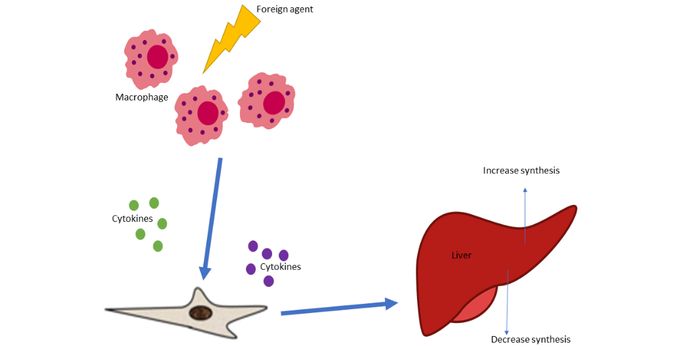

MAR 27, 2023CancerInnate Immunity is a nonspecific host defense mechanism against foreign antigens. It is the first line of defense in a h ...

APR 21, 2024CancerCachexia, defined as a loss of body weight, fat, and muscle mass that occurs in patients with chronic diseases, includin ...

MAY 21, 2023CancerInflammation occurs as a natural response to an insult, such as an injury or a bacterial infection. When your body ...